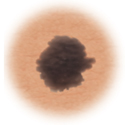

Lunares (nevos)

Son marcas pequeñas en la piel que se deben a las células que producen el pigmento. Los lunares pueden ser planos o elevados, lisos o ásperos y algunos tienen pelos. La mayoría es de color marrón oscuro o negro, pero algunos son amarillentos o del color de la piel. Los lunares pueden cambiar con el tiempo y a menudo reaccionan a los cambios hormonales.

En la mayoría de los casos, los lunares son benignos y no se necesita tratamiento. Algunos lunares benignos pueden convertirse en cáncer de piel (melanoma). A continuación puede consultar los signos de que un lunar se está volviendo canceroso.